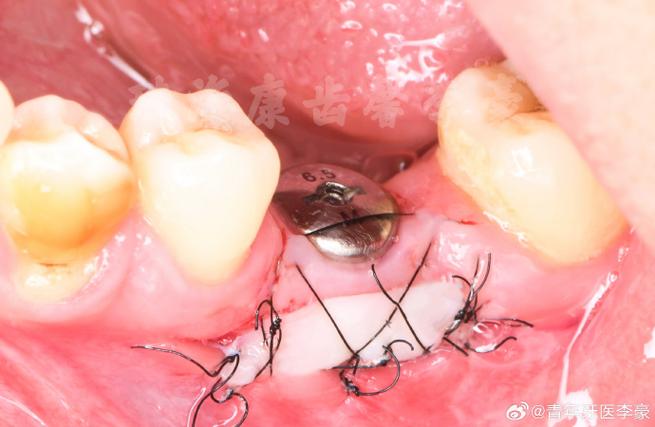

| 移植与固定 | 将取下的牙龈组织修剪后移植到受区,用可吸收线缝合固定(如褥式缝合+间断缝合)。 | 移植组织需无张力贴附,避免扭转;缝合时需覆盖种植体颈部(若存在暴露)。 |